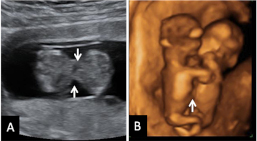

Vemos la ecografía en dos dimensiones (2D) (figura A) de un corte transversal de los abdómenes de los fetos, a la altura del ombligo, mostrando la zona compartida (flechas). En la figura B, podemos observar la reconstrucción en 3D con la flecha señalando la zona compartida. Con los equipos ecográficos actuales este diagnóstico puede realizarse muy pronto. En este caso los gemelos están unidos por un puente fino a la altura de los cordones umbilicales y comparten una parte pequeña de hígado. Por suerte, la separación quirúrgica puede realizarse sin grandes dificultades.